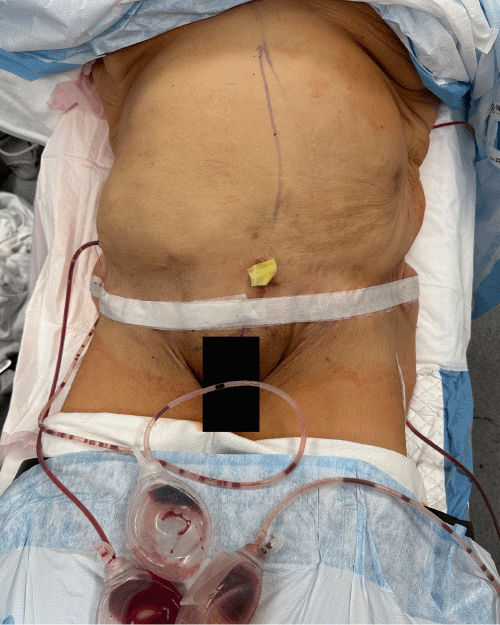

Figure 9. Conclusion of Combined Hernia Repair and Panniculectomy. Published with Permission

Clinical photograph at the conclusion of the procedure, showing the closed abdominal incision and the placement of three JP drains

The anterior rectus sheath was then closed over the mesh. While most of the anterior sheath could be approximated with a running #1 PDS suture, some tension was encountered, and a segment could not be primarily closed. The redundant hernia sac was de-epithelialized and utilized as an interposition flap between these fascial edges to ensure complete mesh coverage (Figure 8). One Jackson-Pratt (JP) drain was placed in the retrorectus space, overlying the mesh. The patient was then placed in a flexed (jackknife) position for completion of the panniculectomy by the plastic surgery team. Excess skin from approximately 2 cm below the umbilicus to the pubis was excised in an elliptical fashion. Two additional JP drains were placed in the subcutaneous tissue pocket created by the panniculectomy, and Scarpa’s fascia was closed with interrupted PDS sutures. The abdominal skin was closed with a running Stratafix™ suture (Figure 9).